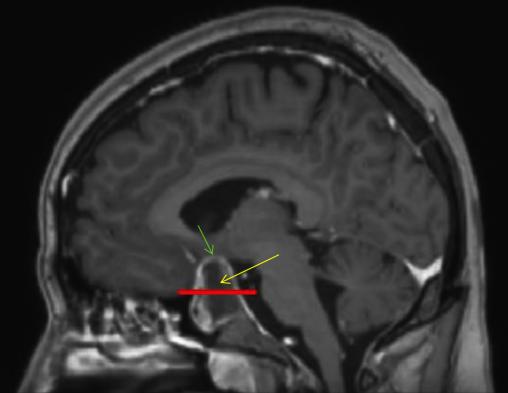

Coupe sagittale d’une IRM cérébrale en séquence T1 avec injection de gadolinium. Les coupes T1 sont des coupes dites « anatomiques » c’est-à-dire que la substance blanche est blanche et la grise est grise contrairement à la séquence T2 où c’est l’inverse. On voit que les vaisseaux sont rehaussés notamment dans le sinus caverneux.La flèche jaune pointe le macroadénome hypophysaire hémorragique. La ligne rouge représente la limite virtuelle de la loge pituitaire. La flèche verte pointe le chiasma optique comprimé par la masse.